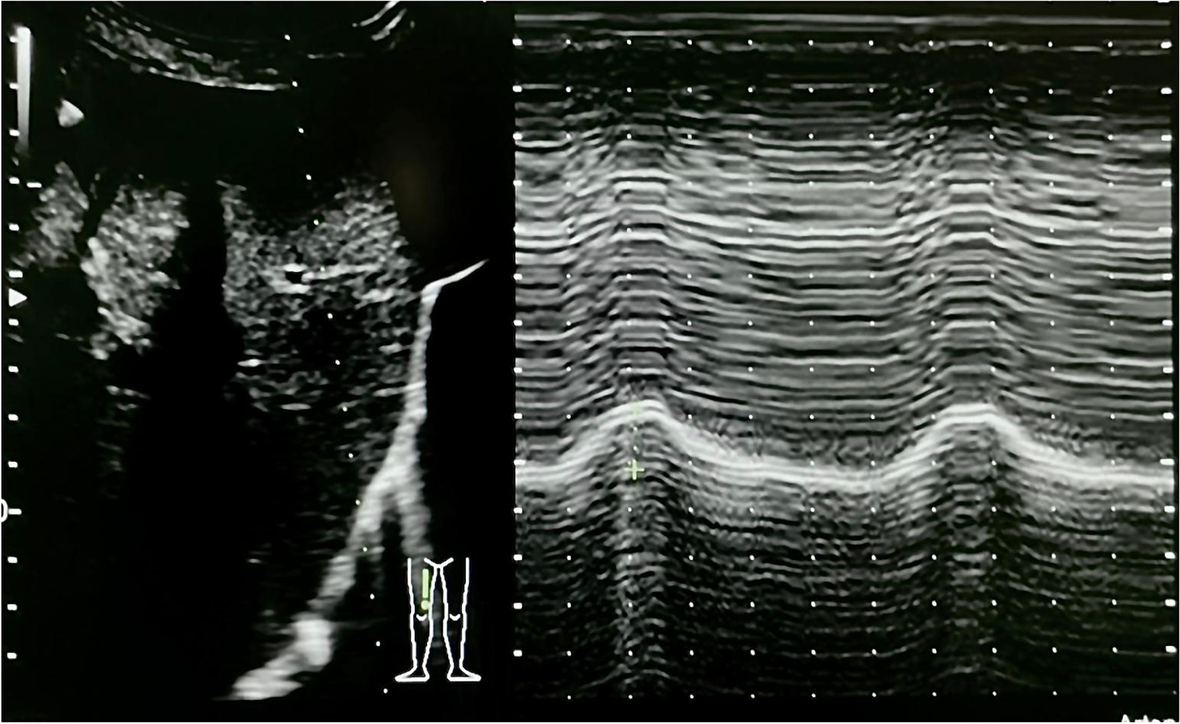

A 39-year-old vaccinated woman was admitted to our emergency department with dyspnea and respiratory failure with a positive nasopharyngeal molecular swab test for SARS-CoV-2 infection. After 6 days of O2 therapy, the patient was transferred to the intensive care for respiratory worsening requiring non-invasive ventilation (NIV) with a helmet (FiO2 60%, PS 8 cmH2O, PEEP 12 cmH2O). For the further 6 days, the patient alternated NIV and high flow nasal oxygen (HFNO) (FiO2 50%, flow 60 L/min) until, after an episode of desaturation and respiratory distress with visual analogic scale (VAS) for dyspnea of 6 (on a 0-10 scale), required tracheal intubation, and she was transferred to intensive care for invasive mechanical ventilation. The respiratory gas exchange and chest x-ray slowly improved in the following 7 days (arterial blood gas on the 7th day: pH 7.38, PaO2 231 mmHg, PaCO2 47 mmHg, HCO3 28.1 mmol/L, BE 2.6 mmol/L, Lactate 1.20 mmol/L), and we attempted to wean the patient from the ventilator reducing the pressure support to 8 cmH20 with 5 cmH2O of PEEP, however, without success. Clinically, the patient showed increased accessory respiratory muscles’ fatigue, and the PaCO2 increased > 100 mmHg; tidal volume (Vt) was less than 300 mL with respiratory rate (RR) of 26/min. After 2 unsuccessful attempts of reducing pressure support, she was tracheostomized [1, 2]. Just after the second weaning attempt and before performing the tracheostomy, point-of-care ultrasonography (POCUS) with low-frequency probe (Hitachi, Arietta 65, Tokyo 110-0015 Japan) revealed a lung ultrasound score (LUS) of 8 and with high-frequency probe diaphragmatic weakness with a thickening fraction (TF) < 20% (normal value between 20 and 30%). TF was measured as the maximal diaphragm thickness during inspiration (Tdi, pi) minus the diaphragm thickness at end-expiration (Tdi, ee) divided by the Tdi, ee, and multiplied by 100. Ultrasonographic diaphragm assessment was performed while the patient was ventilated with pressure support ventilation of 8 cmH20 and 5 cmH2O of PEEP; in the supine position, the diaphragmatic excursion was < 1.3 cm (normal value > 1.8 cm) [3] (Fig. 1 and supplemental video 1). Supplemental video 2 showed TF measurement.

Fig. 1

A low-frequency (3.5–5 MHz) ultrasound transducer is used to identify the right hemidiaphragm. The M-mode then is employed to show movements and measure diaphragmatic excursion (cm)